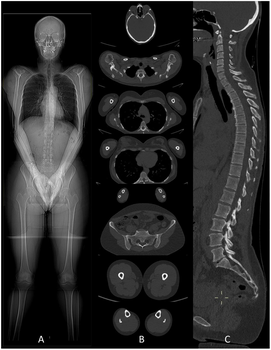

Disposant de toutes les modalités d'examen (Imagerie par Résonnance Magnétique (IRM), scanner, artériographie diagnostique et interventionnelle, échographie, mammographie, radiologie générale) et fort d'une équipe de 30 radiologues et 4 médecins spécialistes en formation, le Service d'Imagerie médicale de la Citadelle exerce son activité sur 4 sites (Citadelle, Herstal, Laveu et Valdor).

Prise en charge de l’anévrisme de l’aorte abdominale. Comment y faire face ?